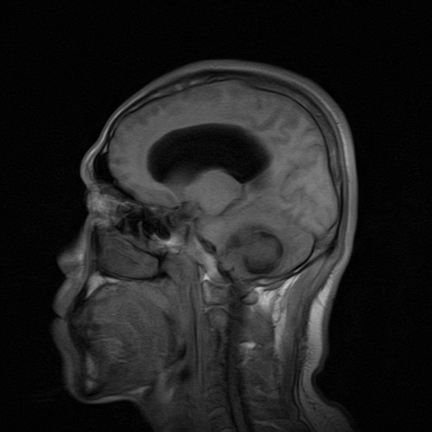

标题: MRI2064:少见病例。男性52,视力下降多年。 [打印本页]

标题: MRI2064:少见病例。男性52,视力下降多年。

四脑室区见混杂信号占位影,脑室系统扩张明显,临近结构显著受压称位,患者52岁,多考虑室管膜瘤可能性大

定位;脑室内富血供占位

应该是来源于小脑蚓部的占位,如血管母细瘤或星形细胞瘤

考虑第四脑室室管膜瘤并梗阻性脑积水;部分性空蝶鞍;左侧上颌窦粘膜下囊肿。

小脑蚓部胶质脑膜瘤突入四脑室;肿瘤内见血管流空信号和钙化信号.

比较典型的脉络丛乳头状瘤并脑积水,鉴别小脑蚓部血管母细胞瘤。